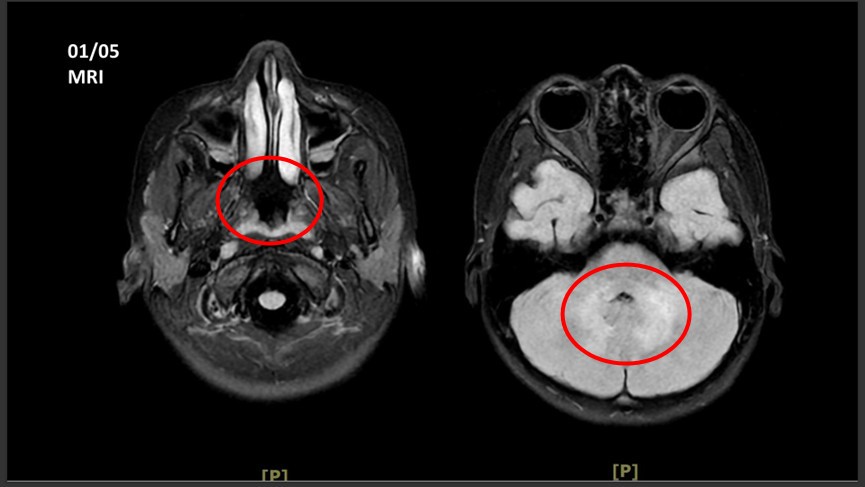

這起病例的診斷過程極具挑戰性,因為女童在 2025 年 11 月發病初期雖有感冒病史,卻始終沒有明顯發燒,導致家人一度誤以為僅是一般感冒。直到今年 1 月初門診追蹤時,王傳育主任發現女童已出現小腦與大腦功能異常,表現為走路偏右、反應呆滯、拿東西不準確,甚至出現血壓偏高與心跳變慢等腦壓升高的徵兆。透過核磁共振(MRI)掃描,醫療團隊在女童的小腦及大腦白質發現多處異常訊號,證實神經系統已發生發炎性脫髓鞘病變。